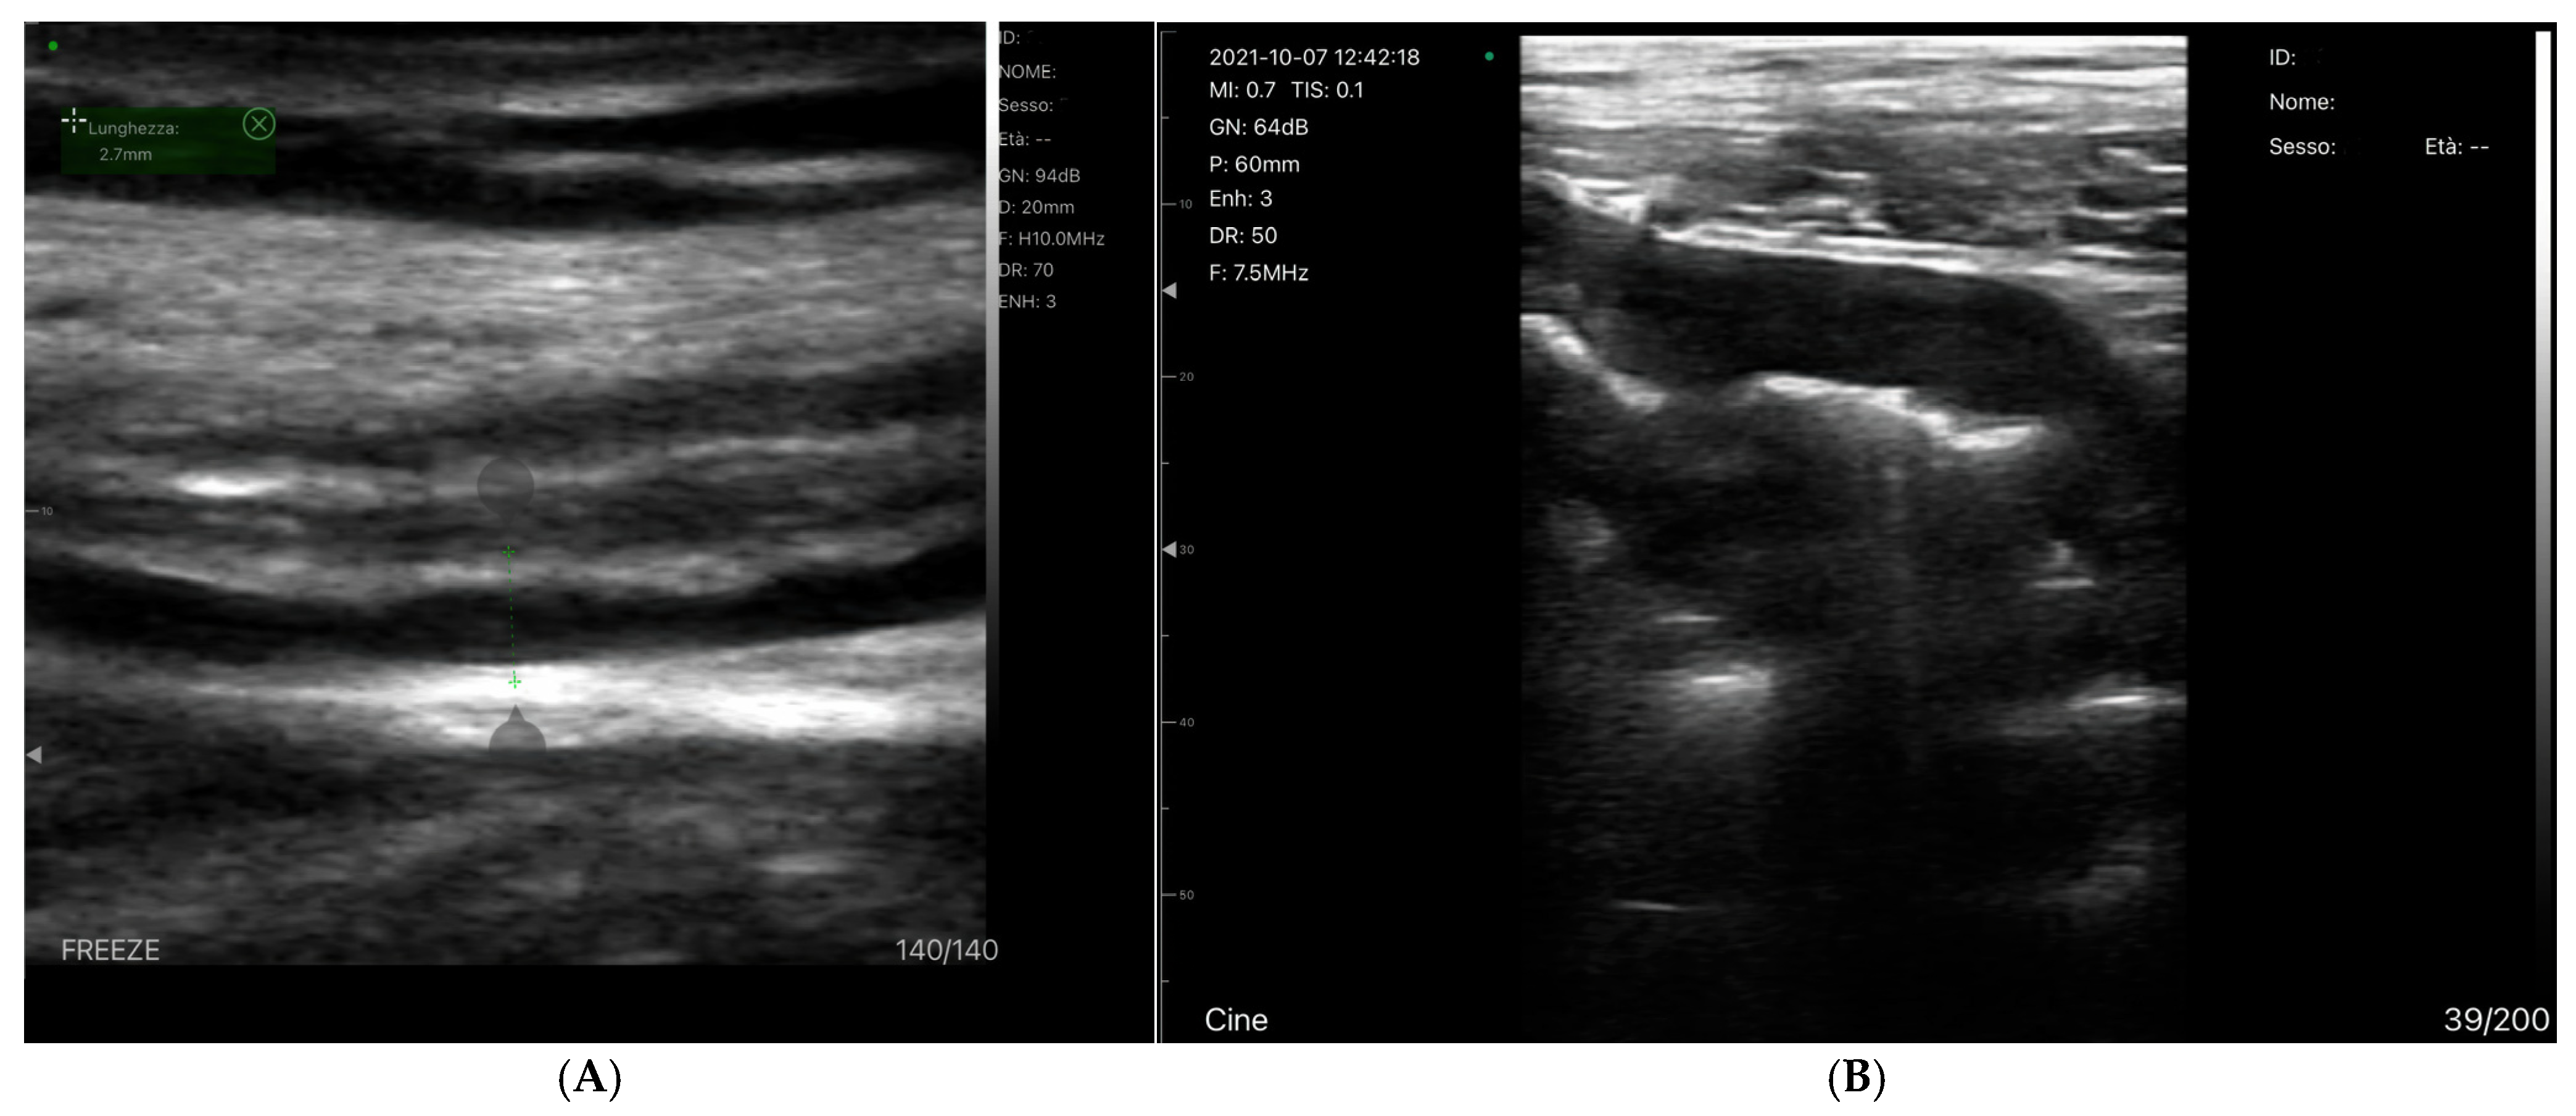

3.1.1. B-Mode

Bowel-Wall Thickening

Venous Congestion